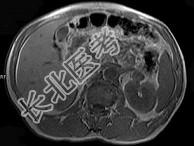

- 单项选择题男,52岁, 下肢无力伴多饮多尿2年余,实验室检查: 低血钾,血醛固酮水平及24小时尿醛固酮定量超过正常值, MRI检查如图所示,应诊断为 ( )

A、左肾上腺囊肿

B、左肾上腺腺瘤

C、左肾上腺嗜铬细胞瘤

D、左肾上腺髓脂瘤

E、左肾上腺转移瘤